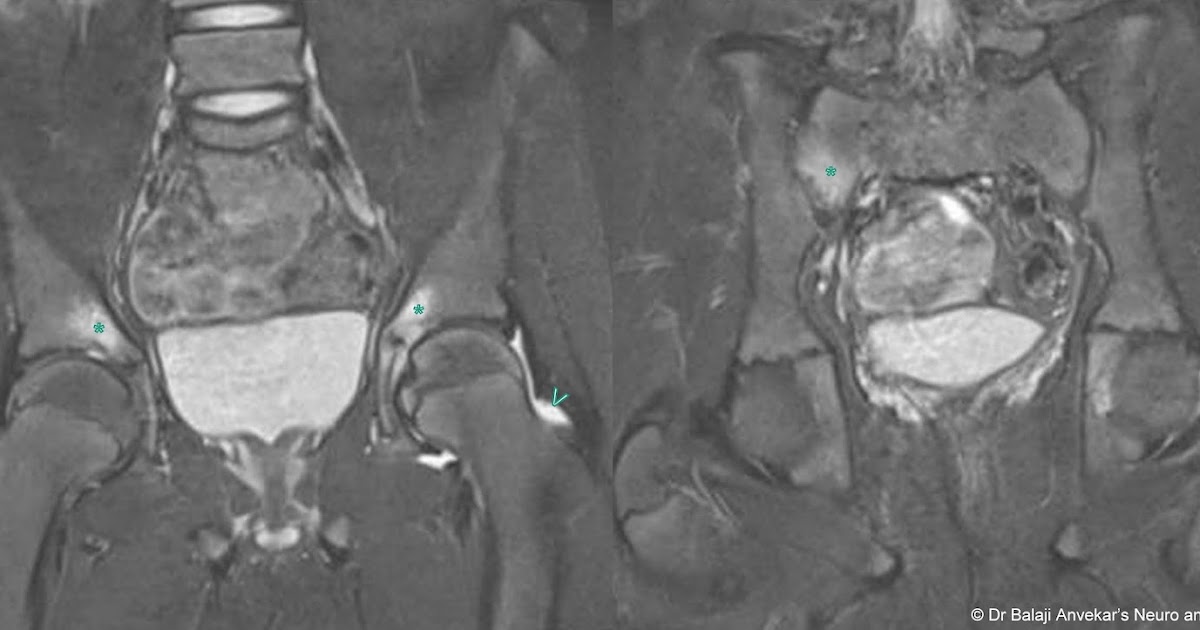

From www.neuroradiologycases.com

Dr Balaji Anvekar FRCR Vitamin C deficiency mimicking inflammatory Vitamin C Deficiency Radiology Serum vitamin c levels can be obtained to confirm the diagnosis of scurvy. in modern times scurvy is a rarely encountered disease caused by ascorbic acid (vitamin c) deficiency. in addition, it has significant antioxidant properties that protect cells from free radical damage. Scurvy is a disease caused due to deficiency of vitamin c. scurvy is a. Vitamin C Deficiency Radiology.